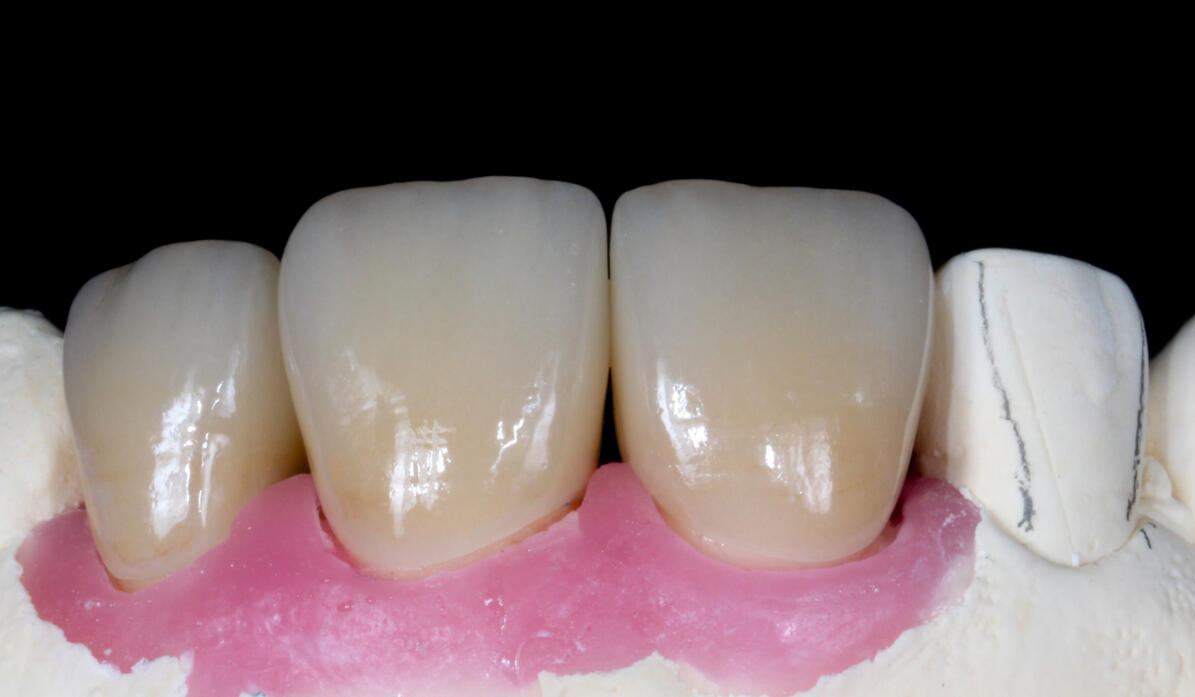

základy plánování, volba materiálu a práce s ním od preparace po fixaci

základy estetického plánování

prezentace úspěšných i neúspěšných případů